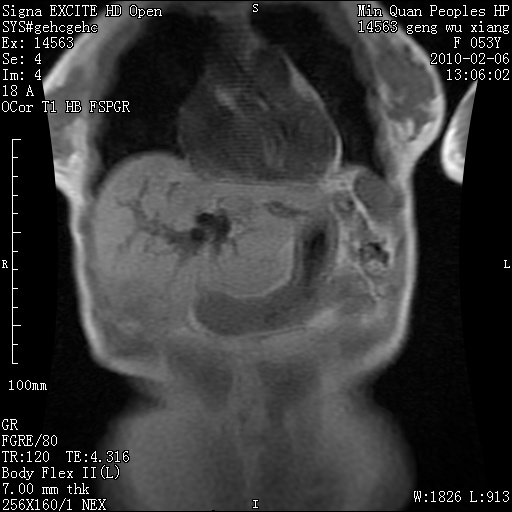

标题: MRI2762:胆道梗阻原因?

f,53y,全身黄染多日。

高位胆道梗阻 胆管癌可能性大

支持 高位胆道梗阻 胆管癌可能性大。